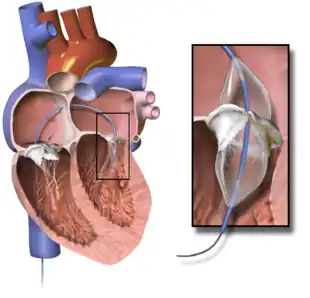

Valvuloplasty

Mitral valvuloplasty is a minimally invasive therapeutic procedure to correct an uncomplicated mitral stenosis by dilating the valve using a balloon. Under local anaesthetic, a catheter with a special balloon is passed from the right femoral vein, up the inferior vena cava and into the right atrium. The interatrial septum is punctured and the catheter passed into the left atrium using a "trans-septal technique." The balloon is sub-divided into 3 segments and is dilated in 3 stages. First, the distal portion (lying in the left ventricle) is inflated and pulled against the valve cusps. Second, the proximal portion is dilated, in order to fix the centre segment at the valve orifice. Finally, the central section is inflated, this should take no longer than 30 seconds, since full inflation obstructs the valve and causes congestion, leading to circulatory arrest and flash pulmonary edema.

With careful patient pre-selection, percutaneous balloon mitral valvuloplasty (PBMV) is associated with good success rates and a low rate of complications. By far the most serious adverse event is the occurrence of acute severe mitral regurgitation. Severe mitral regurgitation usually results from a tear in one of the valve leaflets or the subvalvular apparatus. It can lead to pulmonary edema and hemodynamic compromise, necessitating urgent surgical mitral valve replacement.

Other serious complications with PBMV usually relate to the technique of trans-septal puncture (TSP). The ideal site for TSP is the region of the fossa ovalis in the inter-atrial septum. Occasionally, however, the sharp needle used for TSP may inadvertently traumatize other cardiac structures, leading to cardiac tamponade or serious blood loss.